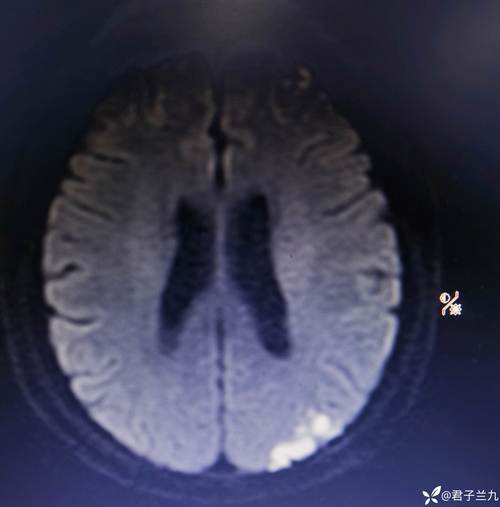

- 头部MRI:特别是DWI序列(弥散加权成像),对发现新鲜的、甚至是陈旧的微小梗塞灶非常敏感,这是确诊“无症状脑梗”的主要方法。